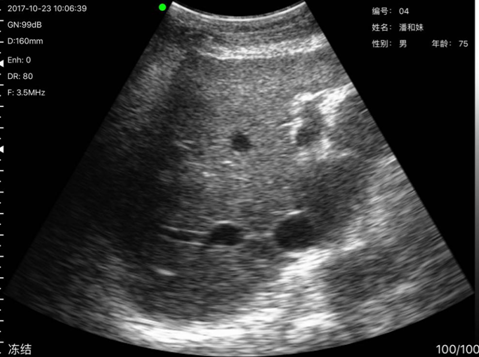

病例4,姓名:潘x妹,性别:男,年龄:75岁通过本次掌上B超检查,发现其肝部异常,经上级医院确诊肝囊肿。